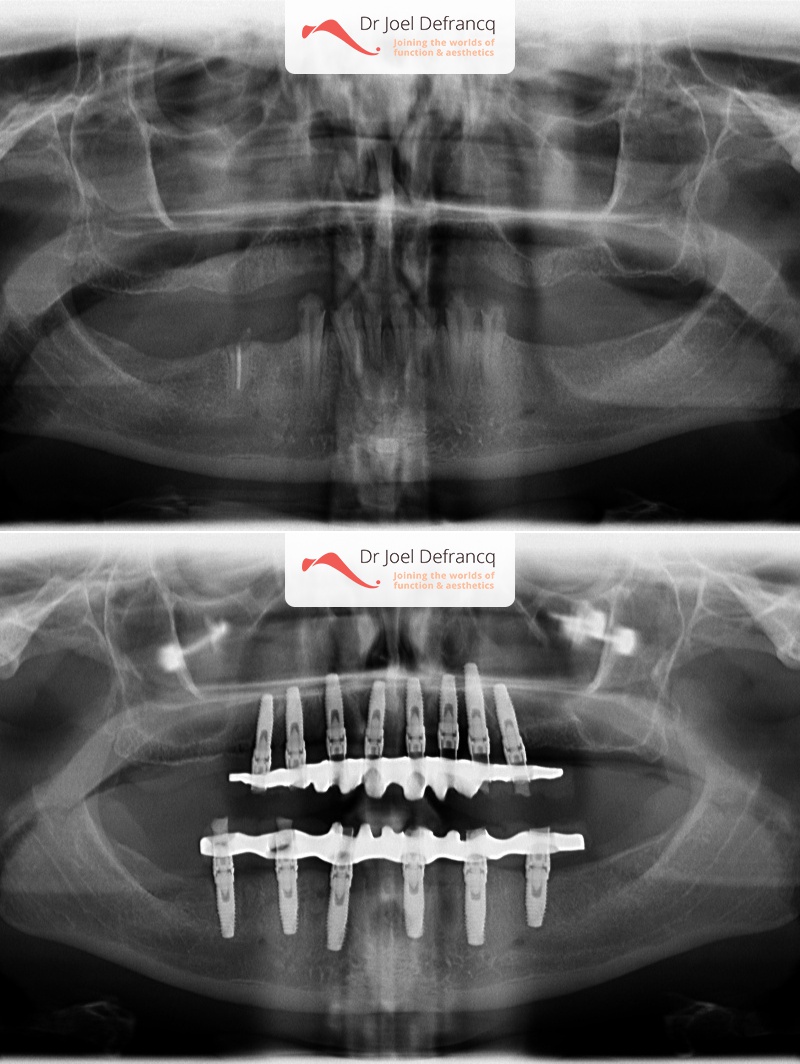

Magdalena: teeth on implants in one week (immediate loading)

Dentale diagnose

- Verloren rest-dentitie

Behandeling tandheelkundige implantaten

- Vaste tanden op implantaten (bovenkaak)

- Vaste tanden op implantaten (onderkaak)